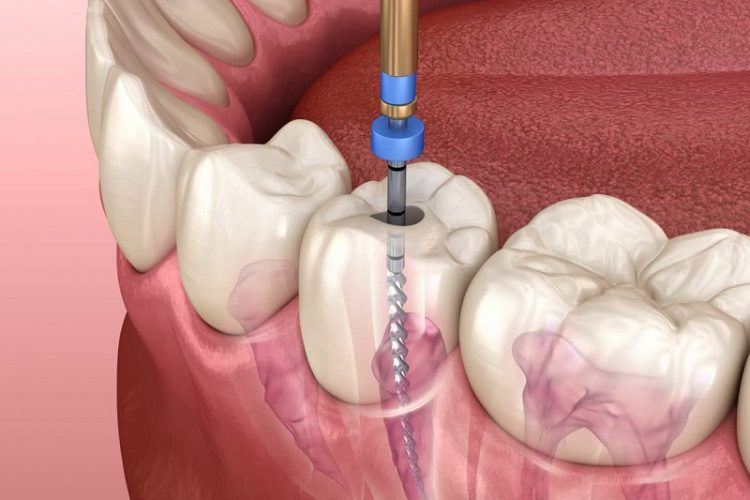

عصب کشی - درمان ریشه

احیای مجدد دندان درمان ریشه دندان یا Root canal therapy یا اندو، به عمل درمان مجرای اعصاب دندان که همان...